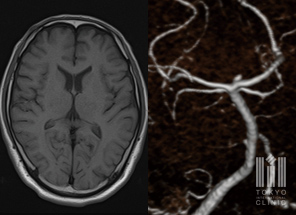

頭部MRI/頭頚部MRA検査

脳梗塞や脳出血など、脳の組織や血管に異常がないかを検査します。医療被ばくの心配がありません。